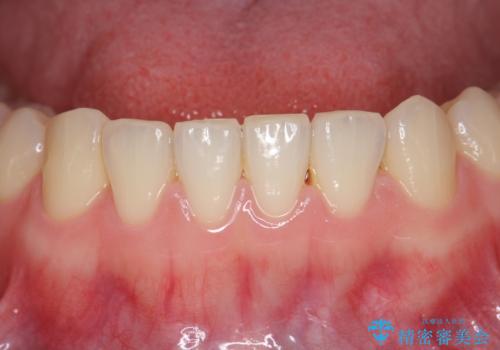

下の前歯が1本短い インビザラインと部分矯正の組み合わせ

- 前歯のガタつきと、下の前歯が一本短いことを主訴に来院。

インビザラインのマウスピースではめる装置で歯を引っ張り出すことは難しいと説明し、下の前歯だけワイヤー部分矯正を行ってからインビザライン矯正で仕上げをしました。

周りには気にしなくていいのではと言われていたが、やってよかったと非常に満足されていました。

難しい部分を短期間ワイヤー矯正を行ってからのインビザラインは、全体治療が短くなるだけでなく、仕上がりもよくなるのでオススメです。